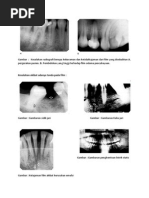

Gambar 10.4 memperlihatkan perubahan tulang kepala kondilus dan eminensia

artikularis yang terlihat dari pandangan sagital radiograf.

Gambar 10. 4 Bentuk kepala kindilus dan eminensia artikularis yang terlihat dari arah sagital. a. Tidak

ada perubahan tulang b. osteophyte c. flattening d. sclerosis e. erosi f. pseudocyst.